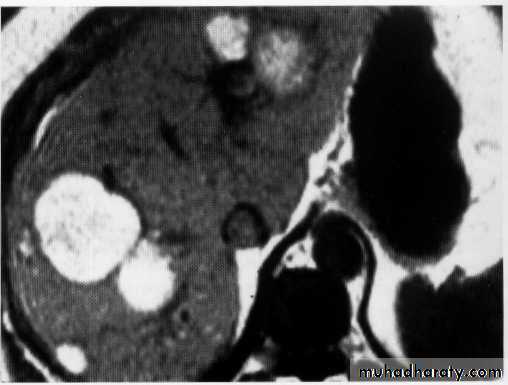

Hepatoma + met.

hemangeoma

Liver abscess

Hepatic , renal cyst